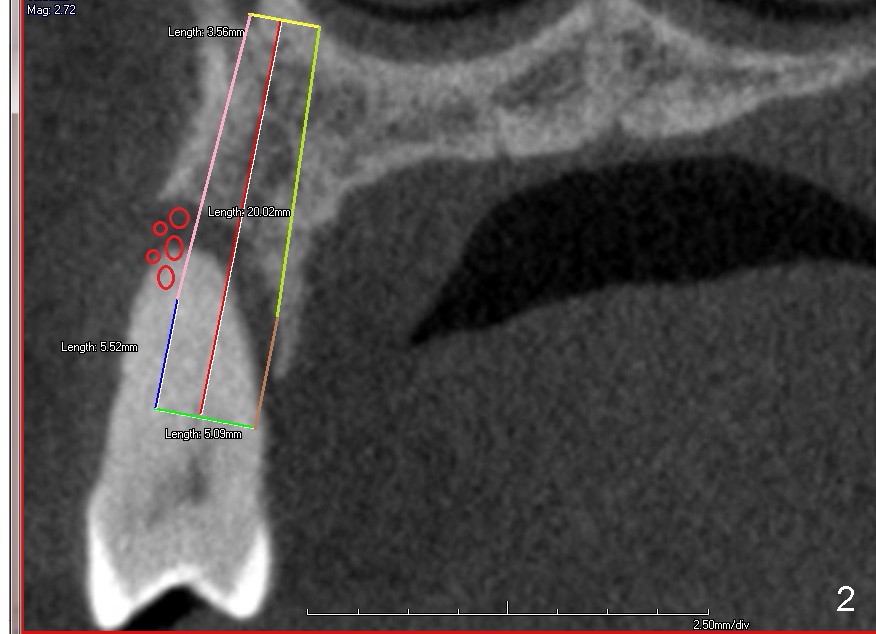

Immediate implant at the site of #13 is the last implant to be placed for full mouth reconstruction (Fig.1 CT sagittal section; 1 2 3 4 5 6 7 8). The sequence of the treatment is due to insurance benefit issues. In fact brackets for orthodontics were dislodged due to carelessness by the patient. He does not want to pursue this mode of treatment. Either prior to or after implant placement, bone graft will be placed distally (Fig.1: in large amount (red circles)) and buccally (Fig.2 (coronal section). If primary stability is acceptable, an immediate provisional is fabricated. He will be traveling abroad soon.

Fig.5 is an illustration showing the socket after extraction. The osteotomy is intentionally placed distally (Fig.6 arrow: pilot drill). In case the patient agrees to have ortho treatment, there will be space to correct the upper midline (7). If not, a molar crown will be fabricated. By the time a 4.5x20 mm tap is inserted (Fig.7 T), the mesial gap is visible (*). When a 6x20 mm implant is placed (Fig.8 I), bone graft is placed buccally (Fig.2, as planned) and mesially (Fig.8 red circles, as compared to Fig.1). The implant has to be as large and long as 6x20 mm to get primary stability (insertion torque 50/60 Ncm). The apex of the implant is close to the sinus floor (Fig.8 ^) or in fact the nasal floor (Fig.9 N). There appears bone growth in the mesial gap 3 months postop (Fig.10 *). There is no bone loss 2.5 years post cementation (Fig.11).